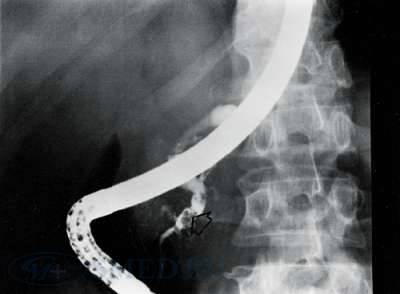

Рис. 5. ЭРХПГ. Стрелкой указан конкремент в протоке поджелудочной железы.